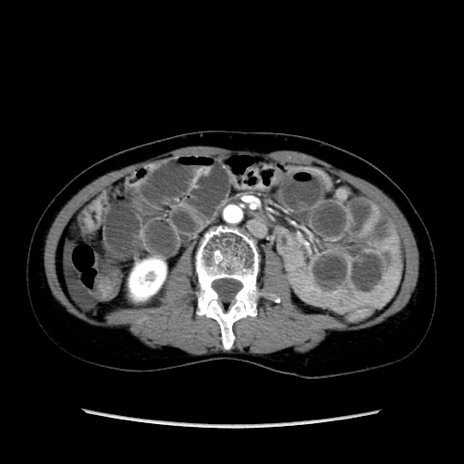

症例32(横断像)

【症例】40歳代 女性

【主訴】上腹部痛、嘔気・嘔吐

【現病歴】約9時間前頃から急に上腹部痛、嘔気、嘔吐が出現。改善しないため救急要請。

【既往歴】子宮頚癌(広汎子宮全摘術、放射線療法)、腸閉塞

【身体所見】腹部:平坦、軟、腸雑音亢進、上腹部を中心に腹部全体に圧痛あり。

【データ】WBC 8400、CRP 0.03